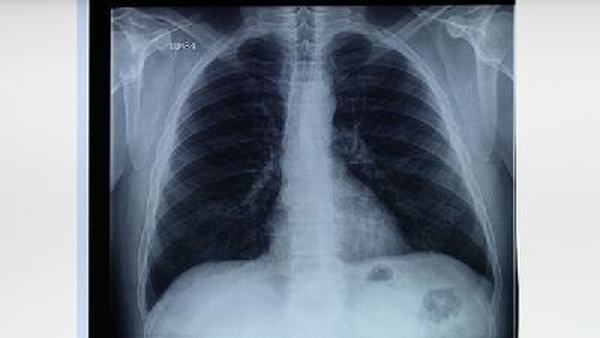

肺纤维化是一种慢性肺部疾病,它会导致肺组织的瘢痕化和纤维化,使肺部变得僵硬,呼吸困难加重。这种疾病给患者的生活带来了极大的困扰,并且在缺乏有效治疗方法的情况下,其预后也相对较差。患者和社会大众对肺纤维化的病因和传播方式都有一定的疑虑,尤其是对于是否可通过接触感染他人。

首先需要明确的是,肺纤维化不是一种传染病。肺纤维化通常是由各种原因引起的,如长期接触有害气体、矽肺、肺炎、结缔组织疾病、药物和放射治疗等。尽管这些因素都可能导致肺纤维化的发展,没有证据表明它们可以通过接触他人来传播。